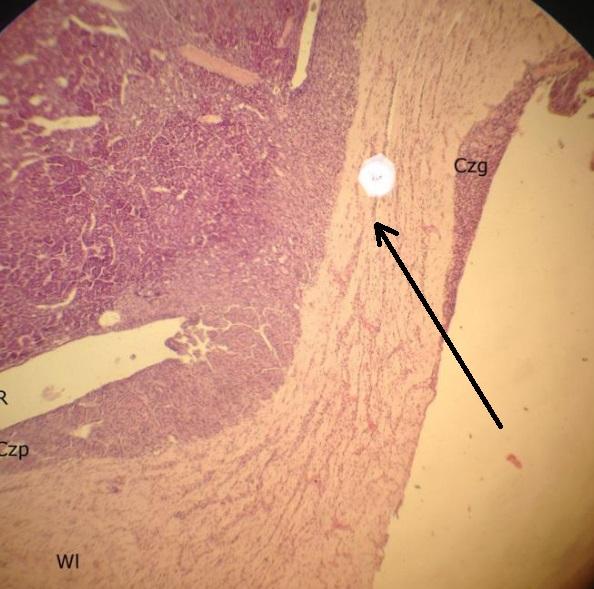

sporych rozmiarów tętnica (tarczyca)